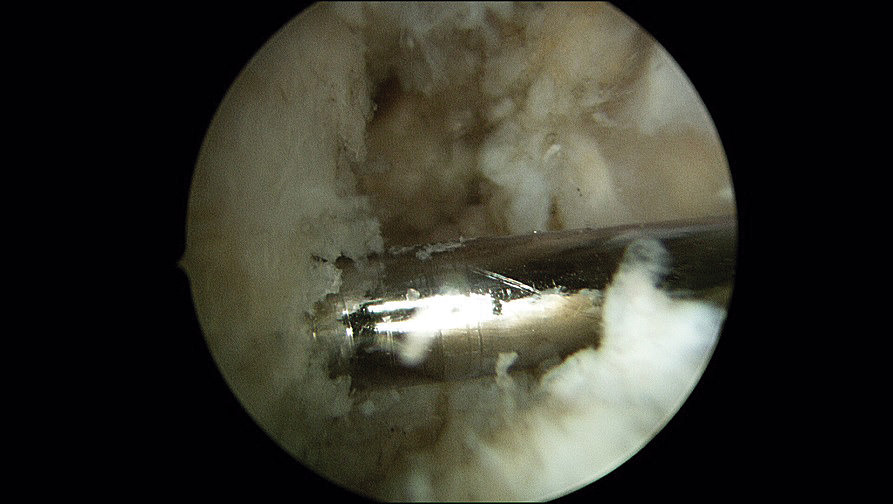

Una vez realizados los 2 túneles, desde el portal anterolateral se inserta el tornillo de biotenodesis de 5 × 15 mm con la plastia colocada hasta la punta del destornillador y se inserta el tornillo siguiendo la técnica (Figura 6).

Figura 6. Tornillo de biotenodesis con la plastia colocada y lista para su introducción.